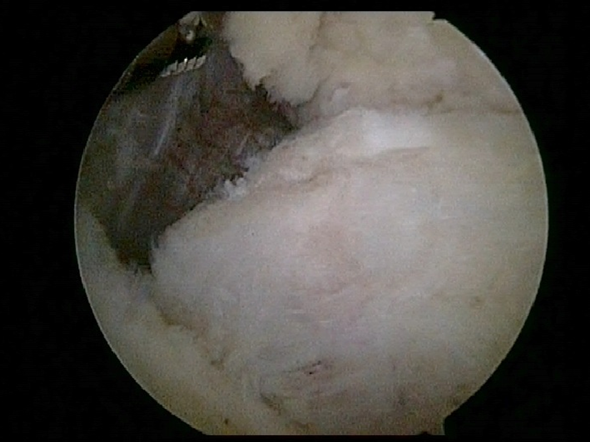

Arthroscopic Treatment For Elbow Arthritis Osteophyte Removal Helps Regain Elbow Function